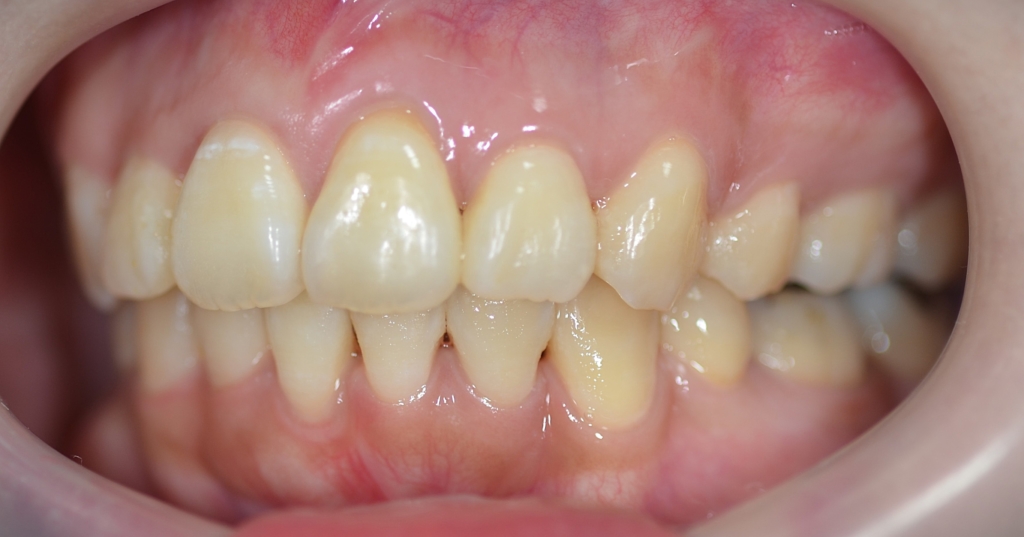

上段が矯正治療前、下段が矯正治療後

歯並びはキレイになり、大きくズレていた上下の歯並びの正中(真ん中)大体一致しました。

【After】

上下の正中がちょっとズレてしまいました。

患者さん的には「コレくらいなら何の問題もありません!」と温かい言葉をいただき許してもらいました。